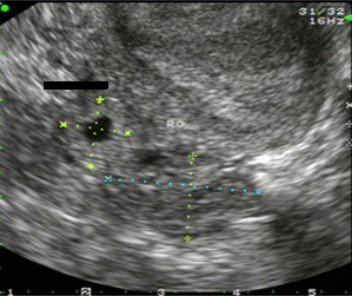

US picture shows adenexal mass with history of IUCD for 10 years?

63.